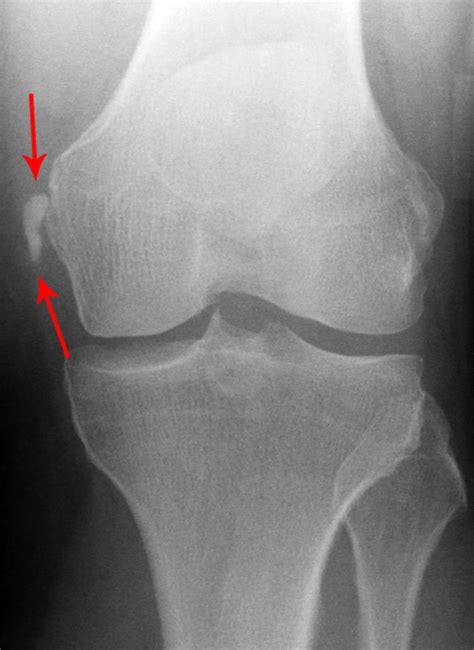

A Pellegrini Stieda Lesion is a rare condition characterized by the calcification of the medial collateral ligament (MCL) of the knee. The MCL is a crucial ligament that provides stability to the inner side of the knee joint. When this ligament becomes calcified, it can lead to pain, stiffness, and reduced range of motion. The condition is named after the Italian surgeon Pellegrini and the German surgeon Stieda, who first described it in the late 19th century.

• Imaging Tests: X-rays, ultrasound, or MRI scans to visualize the calcification and assess the extent of the damage.

• pellegrini stieda lesion xray

• pellegrini stieda calcification